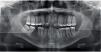

CASE PRESENTATIONMale patient, 31 years of age, refered as his chief complaint: «I want to improve my crooked teeth». In the extraoral assessment a dolichofacial biotype was observed as well as a lower dental midline deviated 2mm to the left in relation to the facial; vertical growth, convex profile and good lip contact. In the intraoral assessment an upper dentoalveolar discrepancy of -8mm and a lower of -7mm was noted; 1mm overbite and 3mm overjet, non-assessable left and right canine class due to disocclussion. The molar relationship was class I on the left side and nonassessable on the right due to first molar absence (Figures 1–4Figures 1 to 4).

Extraoral examination revealed a proper facial balance and profile, a wide smile and the final orthopantomography, an acceptable root parallelism (Figures 6 to 10).